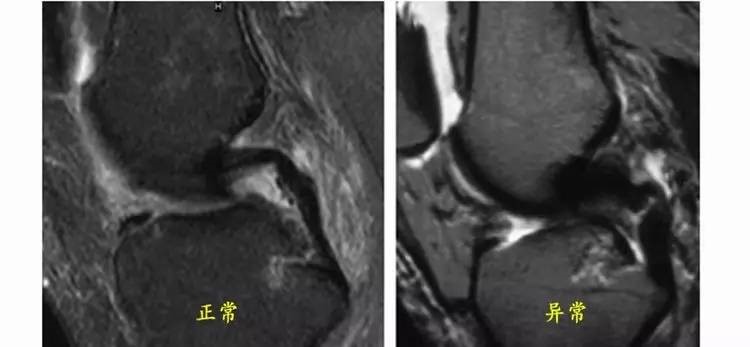

13.gif

ACL损伤的间接征象:指ACL断裂后胫骨前移位出现的一系列改变。间接征象只能考虑可能有ACL损伤。

1.骨挫伤(轴移征):一旦ACL撕裂,胫骨就相对于股骨前移,使股骨外侧髁和胫骨外后方撞击,双方均出现水肿,而且膝关节屈曲的程度决定股骨髁挫伤的部位。